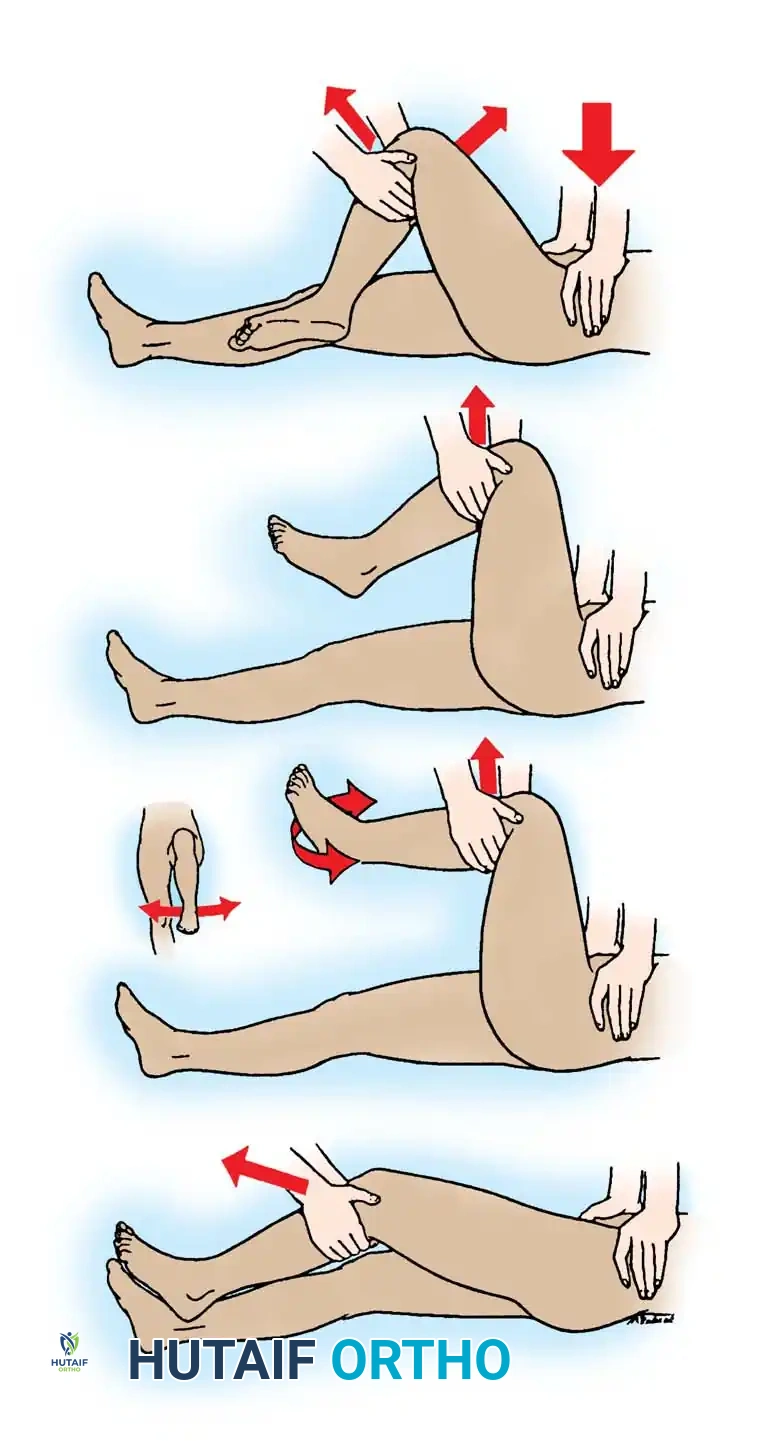

The Allis maneuver is the most commonly utilized technique due to its safety and efficacy in the supine patient.

- The patient is positioned supine. An assistant firmly stabilizes the pelvis by applying downward pressure on both anterior superior iliac spines.

- The surgeon applies steady, inline longitudinal traction in the direction of the deformity.

- While maintaining traction, the surgeon slowly flexes the patient's hip and knee to 90 degrees.

- Gentle internal and external rotation of the hip is applied to clear the posterior acetabular lip until a palpable "clunk" indicates concentric reduction.

Fig. 52-48 (Part 1) Allis reduction maneuver for posterior dislocation of the hip. Initial inline traction and flexion.

Fig. 52-48 (Part 2) Allis reduction maneuver. Application of rotational forces to lever the femoral head into the acetabulum.

The Gravity Method of Stimson

The Stimson method is highly effective and minimally traumatic but requires the patient to be prone, which is often contraindicated in polytrauma patients with spine or thoracic injuries.

- The patient is placed prone on a stretcher with the affected lower extremity hanging off the edge.

- An assistant stabilizes the pelvis.

- The hip and knee are flexed to 90 degrees. The surgeon grasps the proximal calf and applies a steady, downward longitudinal force.

- Gentle rotation aids in guiding the head back into the acetabulum.

The Bigelow Maneuver

The Bigelow maneuver utilizes the intact iliofemoral ligament as a fulcrum. It is more complex and carries a slightly higher risk of iatrogenic femoral neck fracture if performed forcefully.

- With the patient supine and pelvis stabilized, the surgeon grasps the ankle and places their opposite forearm beneath the flexed knee.

- Longitudinal traction is applied, followed by flexion of the hip to 90 degrees in an adducted, internally rotated position.

- The femoral head is levered into the acetabulum through a sweeping motion of abduction, external rotation, and extension.

The East Baltimore Lift

This technique is excellent for minimizing surgeon fatigue and back strain, utilizing the combined strength of two providers.

- The patient is supine. The surgeon and an assistant stand on opposite sides of the affected limb.

- The patient’s hip and knee are flexed to 90 degrees.

- Both providers place their arms under the patient's proximal calf, resting their hands on each other's shoulders.

- By simultaneously standing up from a squatted position, they apply powerful, controlled upward traction while a second assistant stabilizes the pelvis.